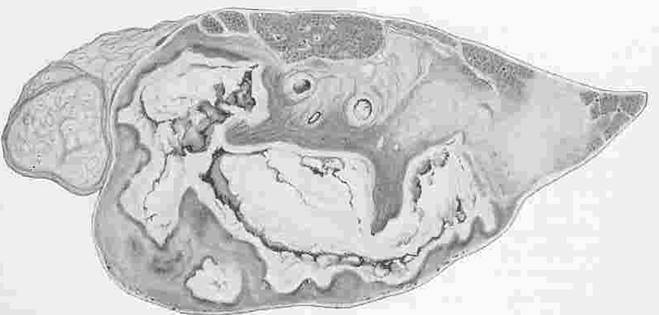

Рис. 30. Кавернозный туберкулез легких КРС

При лобарной пневмонии поражаются целые доли легкого или его обширные участки. Образуются эти участки вследствие слияния отдельных, пораженных туберкулезом долек в одном сплошном поле. Пораженные участки легкого плотные, бугристые, неравномерно окрашенные: серо-белые, желтовато-белые, разделенные прослойками соединительной ткани. При лобулярных и лобарных пневмониях происходит усиленная миграция лейкоцитов из сохранившихся сосудов. Лейкоциты своими ферментами разрушают (разжижают) казеозную массу и превращают ее в гноевидное полужидкое вещество, которое частично рассасывается, а его большая часть удаляется при кашле. После удаления казеозных масс образуются полости, называемые кавернами. В целом, при туберкулезе легких нередко обнаруживают различные по величине туберкулы и очаги пневмонии. Это объясняется неодновременным возникновением этих поражений и разной быстротой их развития, туберкулезный процесс протекает волнообразно: периоды альтерации сменяются периодами пролиферации и заживления.